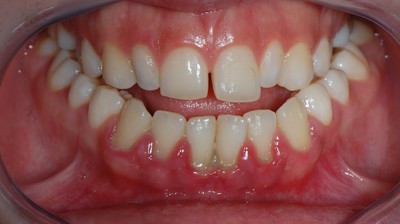

Стадия возникает после законченного процесса лечения пародонтита. Однако это нельзя считать выздоровлением. В стадии ремиссии течение болезни замедляется или приостанавливается.

Характеризуется стадия отсутствием жалоб на самочувствие. Цвет десны — бледно-розовый. Она плотно прилегает к зубам. Отсутствует воспаление, пародонтальные карманы не определяются. Шейки зубов обнажены.

Из этой стадии заболевание может перейти в стадию обострения. Или же наступит полное выздоровление человека.